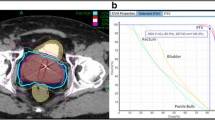

Approximately 2 weeks before treatment planning, 4 gold fiducial seeds were placed transperineally in each patient to allow for motion tracking during treatment. Two of the seeds were implanted at the prostate apex and two were implanted at its base. After allowing time for possible seed migration, treatment planning was performed prior to the treatment day using a CT scan (1.5-mm cuts) with MRI fusion. All pretreatment imaging was performed with the patient in the same position that was used for his treatment delivery. For low-risk patients, just the prostate made up the gross target volume (GTV). For intermediate- to high-risk patients who had a Gleason Score of greater than 6 and a PSA of greater than 15 ng/ml, the proximal half of the seminal vesicles was added to the GTV. After the GTV was delineated, a margin was added to create the planning target volume (PTV). For low- and intermediate-risk patients, the margin was extended 5 mm on all sides except for posteriorly (by the rectum) where a 3-mm margin was used. For high-risk patients, an 8-mm margin was added to the involved side. All patients had the bladder, prostate, rectum, seminal vesicles, and penile bulb contoured; the urethra was not identified.

SBRT was delivered at two dose levels. The first 50 patients (16%) received a total dose of 35 Gy in 5 fractions of 7 Gy each to cover at least 96% of the PTV. The subsequent 254 patients (84%) received a total dose of 36.25 Gy in 5 fractions of 7.25 Gy to cover at least 96% of the PTV. The dose was increased to 7.25 Gy per fraction when preliminary reports at scientific meetings indicated that the higher dose could be delivered safely (based on early results of the study by King et al. of Stanford University; [18]). The mean number of beams was 152 (range, 140–170). The mean D50 to the bladder and rectum was 43% and 41% of the prescribed dose, respectively.

All patients completed the initial EPIC questionnaire prior to treatment. For subsequent time points, the number of patients that completed this questionnaire varied, depending on how many patients reached each follow-up time point and also completed the questionnaire. Figure 2 shows the EPIC scores for bowel, urinary, and sexual QOL. Bowel and urinary QOL scores initially decreased, but then returned to baseline values. For sexual QOL, an overall gradual decrease of about 10% in the QOL score was observed. QOL in each domain was not differentially affected by dose (see Figure 3). To further examine sexual QOL and determine if patients remained potent, we verbally screened patients that were potent prior to treatment (n = 228). At a median 60 months follow-up (range, 48–78 months), 75% percent of them (172/228) stated that they remained sexually potent; 25% of these patients required medication. EPIC QOL scores are presented as a function of dose in Figure 3. In no case was dose a significant determinant of QOL (p < 0.05).